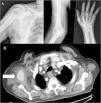

Varón de 83 años, con fibrilación auricular anticoagulado con rivaroxabán, que consulta en urgencias por dolor persistente en hombro derecho con irradiación por cara posterior de brazo, antebrazo y muñeca, que comenzó 10 días antes tras un traumatismo con el miembro superior derecho en abducción forzada. A la exploración se evidencia pequeño hematoma axilar pulsátil, fuerza 1/5 en la extensión de dedos y 3/5 en la extensión de muñeca, hipoestesia en tabaquera anatómica y primer dedo, y pulsos radiales presentes y simétricos. En radiografías solicitadas no se aprecian fracturas ni luxaciones (fig. 1a).

Con sospecha de afectación de plexo braquial se solicita resonancia magnética (RM) cervical, que resulta normal y electromiografía, que evidencia axonotmesis parcial del nervio radial. También se realiza TC torácica que objetiva una masa ovalada en axila derecha de bordes irregulares y densidad similar a la arteria axilar, por lo que se completa estudio con angio-TC (fig. 1 b) que corrobora que dicha imagen tiene continuidad con esta, diagnosticándose de seudoaneurisma de arteria axilar derecha, hematoma axilar y axonotmesis del nervio radial ipsilateral secundarios a traumatismo cerrado. Se deriva al paciente a cirugía vascular que realiza ecografía-Doppler, drenaje del hematoma y exclusión del seudoaneurisma mediante endoprótesis. Actualmente se encuentra en tratamiento rehabilitador con objetivo de recuperar la fuerza perdida por la lesión y en seguimiento periódico en consultas externas de reumatología y cirugía vascular.